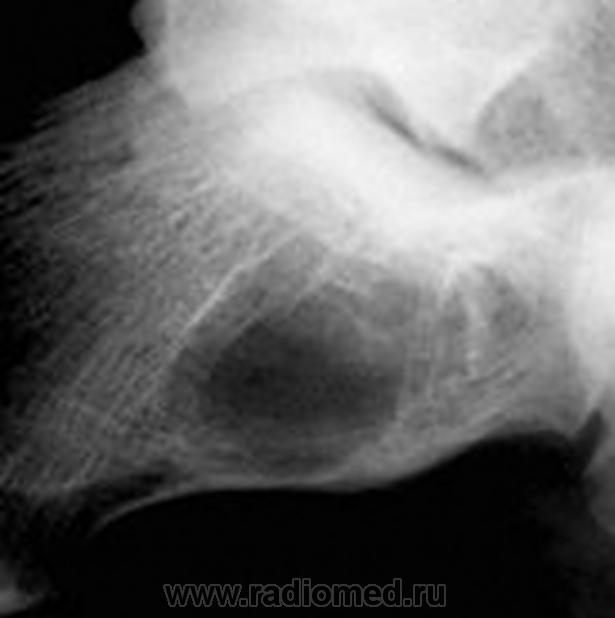

жалобы на незначительные боли в области левой пятки. несколко меяцев назад была травма,после которой полявиась припухлость в области пятки.К врачу не обращался. После мед осмотра в школе направлен на рентгенографию.

Навскидку - костная киста.

Спасибо за быстрый ответ. Я тоже о ней подумала.Но радом еще мелкие полостюшки.

1- псевдокиста пяточной кости, данная локализация характерная, но клинику она обычно не даёт а если и дает то редко, я уже выкладывал случай:

2-остеомиелит, возможно посттравматический;

3- менее вероятно доброкачестванная новообразование;